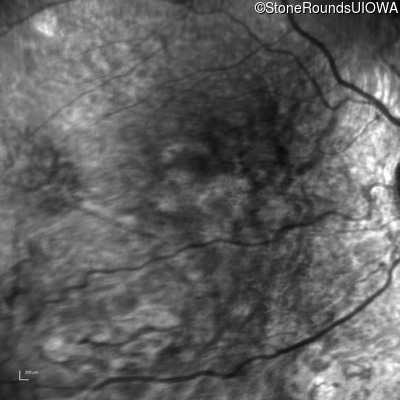

Infrared Fundus Photograph - Right - 20/63 -1

Exemplar